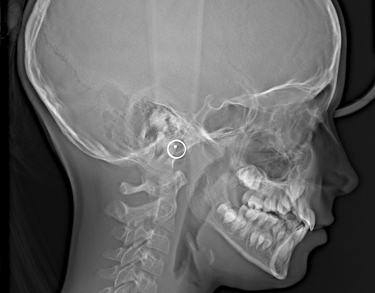

Telerentgenografia boczna (RTG cefalometryczne) – Gdynia

Telerentgenografia w projekcji bocznej, znana również jako RTG cefalometryczne, to jedno z kluczowych badań w ortodoncji i chirurgii stomatologicznej. Umożliwia dokładną analizę układu kostnego twarzoczaszki, proporcji twarzy oraz relacji zębów względem szczęki i żuchwy.

W naszej pracowni RTG stomatologicznego w Gdyni wykonujemy telerentgenogramy boczne, które są niezbędne w diagnostyce wad zgryzu, monitorowaniu postępów leczenia oraz ocenie rozwoju struktur kostnych. Badanie pozwala lekarzowi precyzyjnie zaplanować leczenie ortodontyczne i chirurgiczne, zapewniając bezpieczeństwo pacjenta i wysoką jakość obrazu.